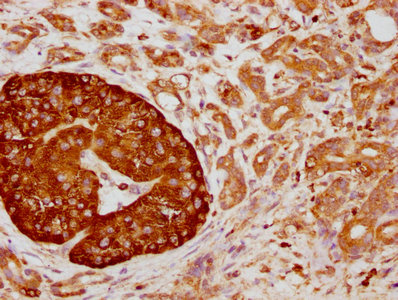

• IHC image of CSB-RA004950A0HU diluted at 1:155 and staining in paraffin-embedded human pancreatic cancer performed on a Leica BondTM system. After dewaxing and hydration, antigen retrieval was mediated by high pressure in a citrate buffer (pH 6.0). Section was blocked with 10% normal goat serum 30min at RT. Then primary antibody (1% BSA) was incubated at 4℃ overnight. The primary is detected by a biotinylated secondary antibody and visualized using an HRP conjugated SP system.